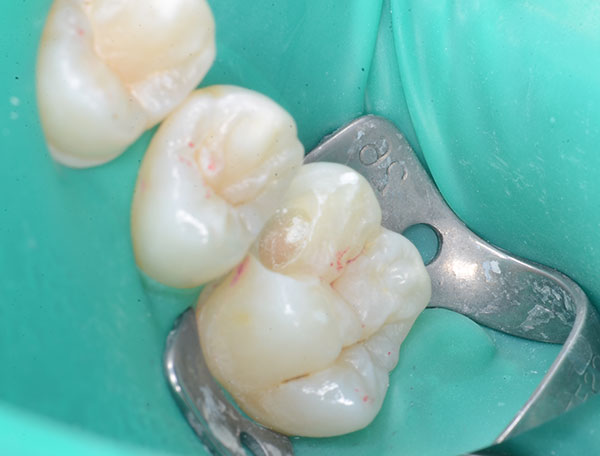

術前

術後

症例について

主訴:

最近冷たい物がよく染みる

治療内容:

炎症を起こした歯髄を部分的に除去し、神経をできるだけ残すことを目的とした治療です。

治療期間:90分 1回

費用:33,000円(税込)

治療に関わるリスクまたは副作用:

経過中に症状が出た場合、根管治療が必要になることがあります。